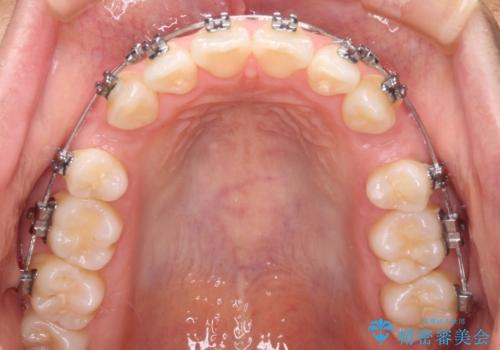

前歯のデコボコを抜歯矯正で改善 メタル装置で費用を抑える

- 矯正装置

- メタルブラケット

- 前歯のデコボコと口元の突出感を気にして来院された患者様です。

非抜歯矯正ではデコボコを解消することでより口元が突出してしまうため、上下左右の小臼歯4本の抜歯を行い、ワイヤー装置による矯正治療を行うこととしました。